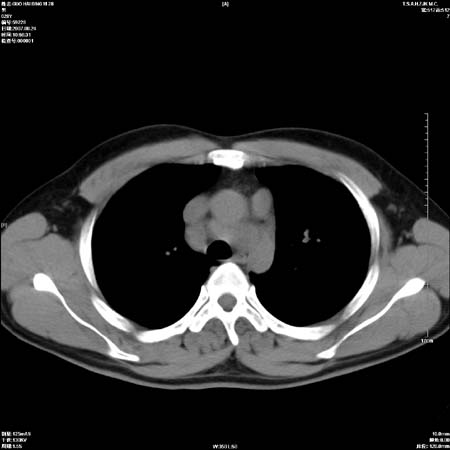

男性,28岁,体检发现左肺病变,患者只有背部隐痛感,哀哉,真不忍心下诊断啊。

左肺门区软组织肿块,左肺上叶支气管开口消失,纵隔内见肿大淋巴结,考虑左中心型肺部,可以做纤支镜取病理确认.

左肺肺门区肿块影,分叶明显,左肺上叶支气管开口受压,纵隔内见肿大淋巴结,考虑左中心型肺癌。

肿块形态影像支持左上叶中央型肺癌伴纵隔淋巴结转移。

左肺门区分叶状软组织肿块,纵隔内有肿大淋巴结,诊断肺癌应该问题不大。